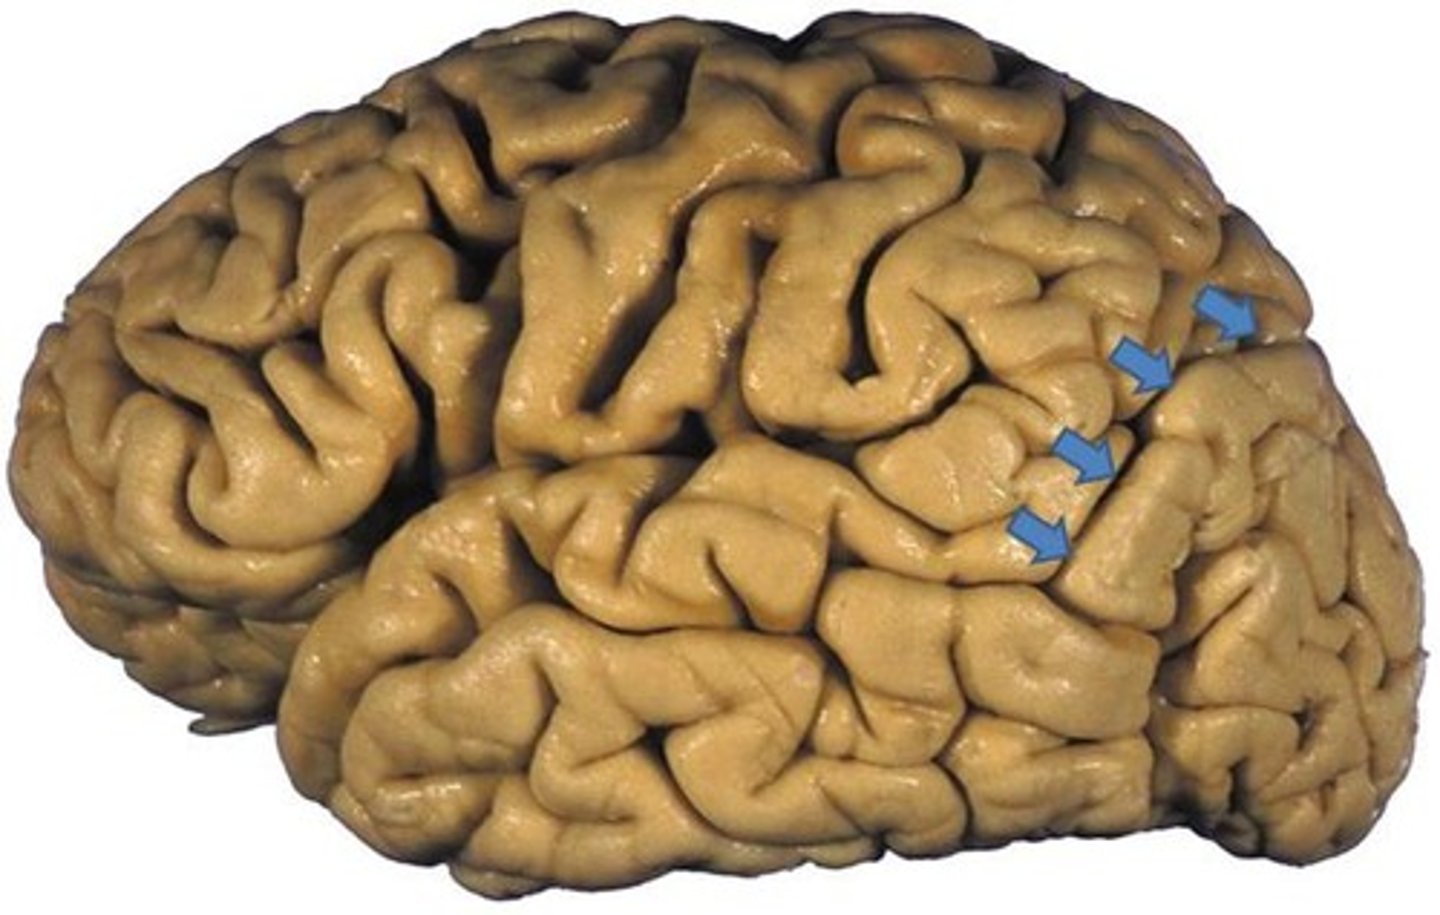

Gyri (gyrus)

ridges of the cortex

Sulci (sulcus)

shallow grooves

Fissures

deep grooves in the brain